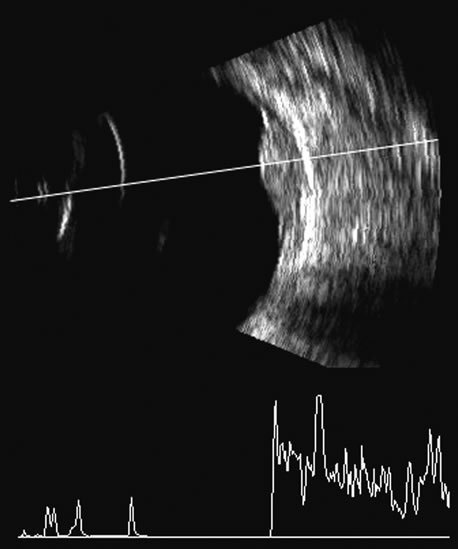

Advances in instrumentation, higher frequencies, and greater sensitivity and resolution have resulted in a continuous improvement in image quality.1 As with any imaging technique, familiarity with the principles and physics of the methodology is necessary to properly recognize the advantages as well as limitations of the technique in a given clinical setting and to minimize difficulties in interpretation of the image. The primary tool for ultrasound evaluation is the use of gray-scale B-scan to delineate tissue boundaries. Ophthalmic ultrasonography remains one of the few areas of medical ultrasonography in which A-scan continues to be used to further differentiate tissue characteristics, such as membrane, retina, tumor, and cyst. Improved B-scan gray scale has reduced some of the advantages of A-scan, but A-scan is still necessary for quantifying echo amplitudes, particularly when distinguishing vitreous membranes from retina or identifying tumor types.2,3

Fresh blood in the vitreous may be acoustically clear since the red cells may not have congealed sufficiently to form a good echo-producing surface.8 A retracted “hyaloid” or posterior limiting membrane (PLM) of the vitreous can be shown with most B-scan instruments, but paradoxically a retracted vitreous may not be seen as well with higher-resolution, more highly focused transducers because they display less area of the reflective surface. Blood collected on the surface of the PLM enhances this surface and may, in some cases, make the PLM resemble a detached retina, since its anatomic dimensions can be similar to the retina. Three differences may help distinguish the two structures. First, kinetic scanning reveals a lack of attachment at the optic nerve for a PLM. Second, the PLM is irregular in reflection and thickness (usually thicker than the retina) between the ora and the disc, and usually the surface cannot be traced forward to the ora on the B-scan display. Third, the amplitude of the echoes from the PLM is lower than from the retina, except when directly perpendicular to the beam, where they may be similar in amplitude. Many of these features of a PLM are demonstrated in Figure 7, whereas Figure 8 shows a typical detached retina.

Fig. 7. This B-scan ultrasonogram demonstrates retinitis proliferans with typical vitreous membrane attaching to the proliferative membrane (arrows) that can resemble a traction detachment. Scanning at right angles helps distinguish proliferative membranes from retinal traction membranes, as they have less reflectivity than retina.

Fig. 8. A retinal detachment (arrow) is very easily detected as a high-amplitude, usually relatively rigid or gently wafting structure connecting always to the optic nerve head in a complete detachment, and usually traceable anterior to the ora serrata. Variations of this pattern can be seen, depending on the plane of the cut and the extent of the detachment, but the height of the echo on A-scan should always be maximal in order to differentiate retina from other, similar membrane formations.